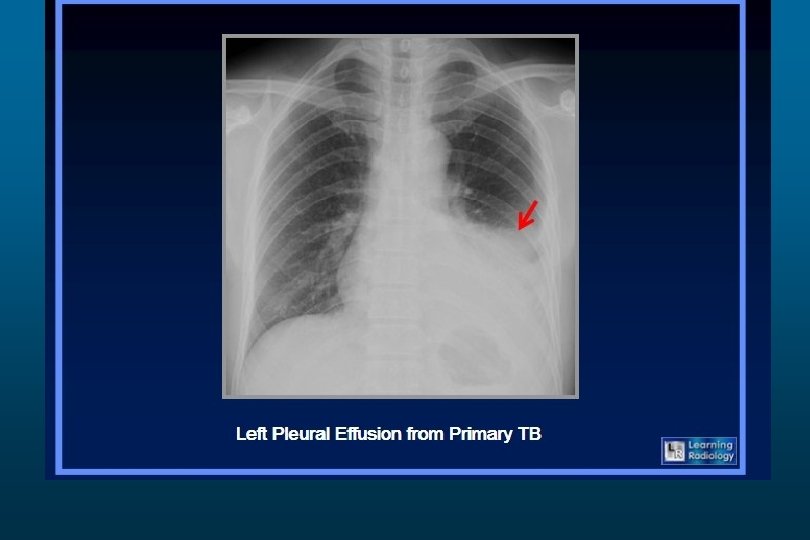

Tuberculosis